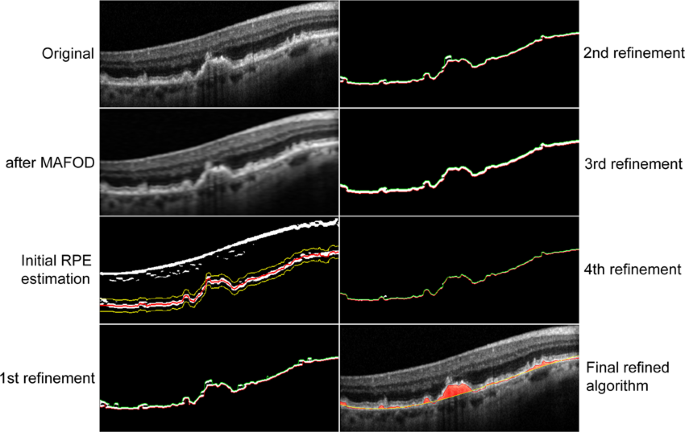

In the first refinement step (Supplemental Fig. 6), we perform the thresholding with respect to both denoised input B-scan and a local histogram equalization of the input B-scan. In the second refinement step (Supplemental Fig. 7), a threshold with respect to the local histogram equalization of the denoised image, and the denoised image itself is selected to binarize the B-scan. In the third refinement step (Supplemental Fig. 8), a Gaussian blur is applied on the denoised image. Then the same steps as in the second refinement step are applied on the smoother version of the denoised B-scan. Finally, in the fourth refinement step, we implemented an improved method for estimating the lower and upper boundaries of the RPE from the segmentation mask by boundary tracing and polynomial fitting (Supplemental Fig. 9). We take the center line between the upper and lower boundary as the final refined estimation of the RPE layer. Figure 1 illustrates the different refinements step-by-step on one B-scan from the original image till the final refined algorithm. More details on the refined algorithm can be found in the supplementary materials.

The input B-scan (left, first row) is filtered with MAFOD filter (left, second row). The retinal pigment epithelium (RPE) is estimated, twofold enlarged and threshold-positive pixels outside a 20-pixel band around the RPE centerline (left, third row; red and yellow indicate the centerline and the 20-pixel band, respectively) are removed (left, last row; green and red indicate the upper and lower boundary of the RPE, respectively). The second, third and fourth refinement steps are applied (right, first, second and third row; green and red indicate the upper and lower boundary of the RPE, respectively) to achieve the final refined algorithm (right, last row). See supplement for details.